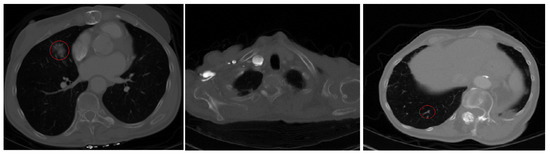

5. Comparison of the Regular Against Double CDNN

We tested these images with standard Convolution Deep Neural Network, used by the authors of [28], against our double Convolution pre-clustered Deep Neural Network with edge sharpening filters. We used this test set of images to determine the threshold or Tx stage in which both networks can detect possibility of cancer. The networks output a decimal value from 0.0 to 1.0, where 1.0 is cancer and 0.0 is cancer-free. We converted this value as a percentage of certainty and multiplied this by 100. The results of the two networks are shown in Figure 8. The drawback here is that we had to decide the minimal value of certainty we would accept as being satisfactory. To fairly compare both networks (regular and double CDNN), we took a mean of their best accuracy value. In Table 2, we can see that the best accuracy of the regular CDNN is 70%, and the best accuracy of the 76%, thus we used 73% as the minimal threshold value for certainty for cancer detection. Taking 73% as threshold for cancerous for both topologies and using this value as a threshold for cancerous, we can see in Figure 8 that our double CDNN detected cancer in stage 3, whereas the regular DNN from [28] did not detect cancer even in stage 4 (late stage). Taking the lower threshold value of 70% (Table 2), the regular CDNN detected possibility of cancer in late stage 4.

Figure 8.

Results of classifying lung cancer images in stage 2, 3 and 4.

Our results were discussed and analyzed with medical personnel from the oncology department, of the hospital in Tetovo, Macedonia. The results were marked as satisfactory, since expert oncologists cannot determine possibility of cancer from a CT scan up to stage 2 or 3. Experts can have doubts of a possibility of cancer from stage 0, but will not schedule a biopsy of the tissue until late stage 2 or 3. The threshold is expected at this stage, since most of the cancerous images used (Section 3.1) for training and testing (Section 3.2) of the algorithms (both standard and double convolution DNN) were mostly from phase T3 or above.